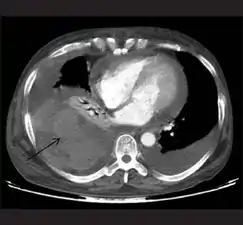

قد يكون استعمال التصوير المقطعي المحوسب مفيدًا في تشخيص تدمي الصدر المحتبس، حيثُ يمكنه تشخيص وجود كمياتٍ صغيرة من السائل بشكلٍ أدق من تصوير بالصدر بالأشعة السينية. على الرغم من هذا إلا أنَّ التصوير المقطعي المحوسب يُستعمل بشكلٍ قليلٍ للتشخيص في حالات الإصابات؛ وذلك لأنهُ يتطلب نقل الشخص المُصاب إلى الجهاز، ويكون بطيئًا ويجب أن يبقى الشخص مستلقيًا.[8][22]

تصوير صدري مقطعي محوسب يُظهر تدمي صدري على الجانب الأيسر (السهم الأسود)، من مضاعفات التهاب المفصل الروماتويدي

تصوير صدري مقطعي محوسب يُظهر تدمي صدري مع رضوضٍ رئوية شديدة